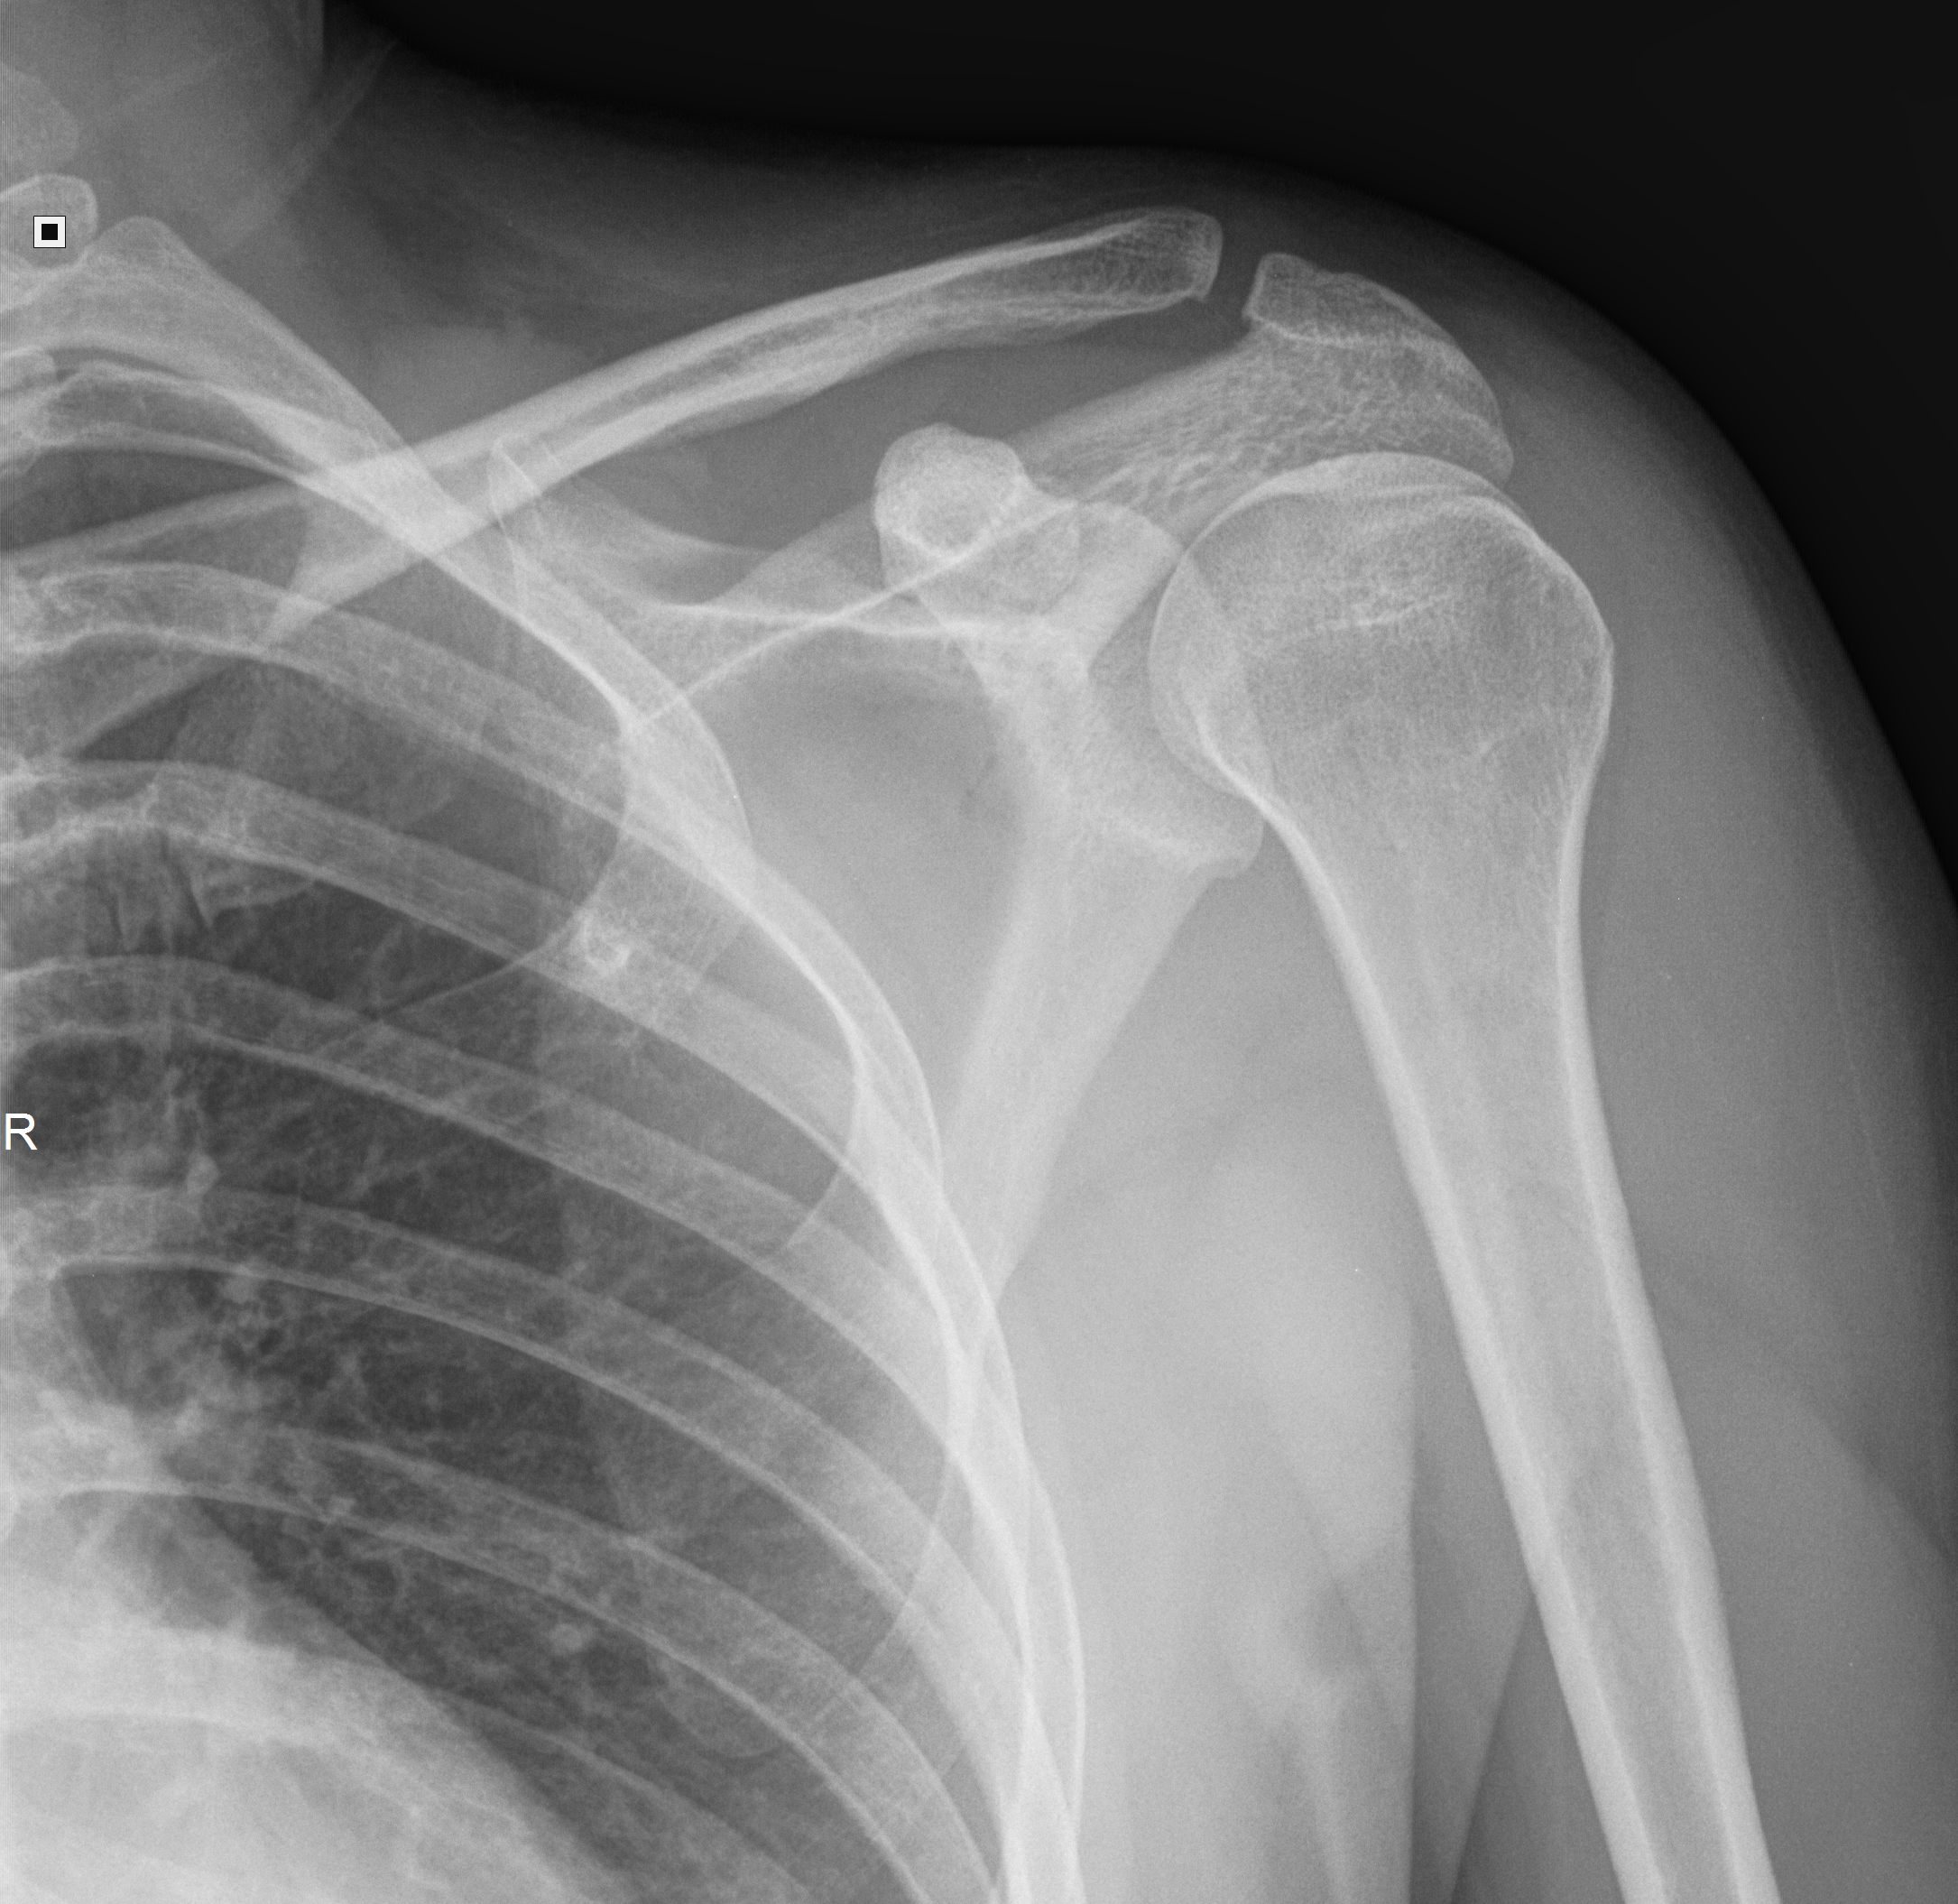

Рентген плеча: примеры снимков и их расшифровка